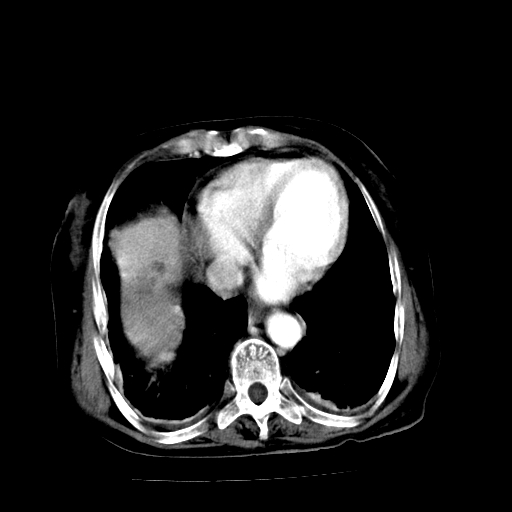

以下是引用随光逐影在2009-4-7 8:21:00的发言:[br]肝内外胆管多发性结石并肝内外胆管扩张;胆系感染。